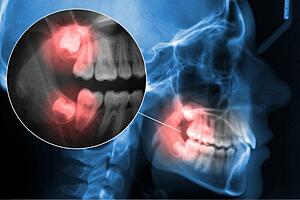

Pourquoi les dents de sagesse posent-elles tant de problèmes ? Les dents de sagesse, ou troisièmes molaires, font généralement éruption entre 17 et 25 ans, une période où l'espace dans la bouche est souvent insuffisant. Dans ce cas, les dents peuvent pousser de travers, être partiellement incluses ou faire pression dans la bouche.